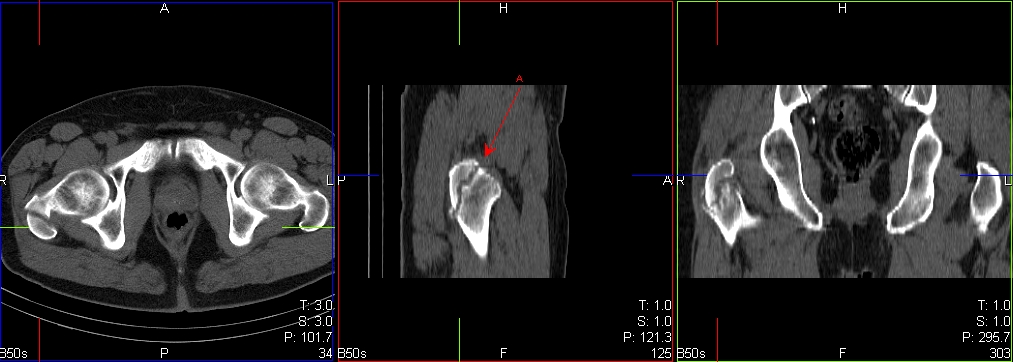

Adult with Right hip pain following trauma, Xrays normal

Whole body blood pool and delayed images

SPECT-CT